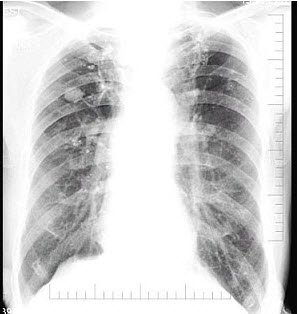

女,36岁,咳嗽,咳痰,咯血,反复发作,CT检查如图,应诊断为()

A.双下肺支气管扩张并感染